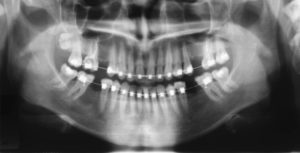

- рентгеновские снимки (ортопантомограмму и телерентгенограмму).

Для анализа диагностических данных были привлечены пародонтолог, стоматолог-терапевт, имплантолог и стоматолог-ортопед, т.к. отсутствие нескольких зубов, дефекты твердых тканей зубов, заболевание пародонта сопутствовали основной патологии. Был составлен план комплексного стоматологического лечения. Предортодонтическая подготовка заключалась в лечении тканей пародонта и устранении дефектов твердых тканей.

В процессе ортодонтического лечения устранялись промежутки между зубами, излишний наклон зубов, скученность. В боковых отделах верхнего и нижнего зубных рядов, на месте отсутствующих зубов, создавались адекватные промежутки для будущей имплантации и протезирования.

Планировалась имплантация в области 3-х отсутствующих зубов: 2-х жевательных на нижней челюсти и одного на верхней челюсти справа. На верхней челюсти слева было принято решение устранить дефект зубного ряда установкой мостовидного протеза, т.к. зубы, граничащие с промежутком, депульпированы и имеют значительные по объему реставрации.

Сделан панорамный снимок для визуализации положения корней зубов и проведения необходимых измерений.

Проведен первый этап имплантации.

Комплексный подход в лечении пациентки позволил успешно решить все стоматологические проблемы. Установка имплантов на этапах ортодонтического лечения сократила общую продолжительность лечения без ущерба для остеоинтеграции. Протезирование полностью восстановило жевательную функцию с максимальным эстетическим результатом. Плотные межзубные контакты, правильное положение осей зубов по отношению к базису челюсти, адекватное распределение жевательной нагрузки создают условия для ремиссии пародонтита.